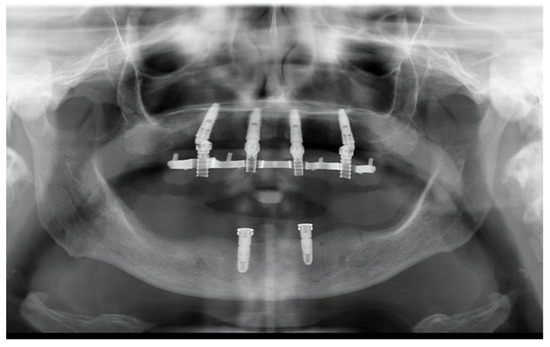

- Accuracy was tested by means of direct vision and tactile sensation, performed by applying alternately pressure on the aluminum try-in, and then the definitive metal framework (Alternate Pressure Technique), secured without screws, to determine if any movement occurs. In addition, the one-screw test proposed by Jemt and co-workers was performed in case of doubts occurred [11]. No discrepancy of the radiopaque, aluminum try-in, secured with only one screw tightened, was observed [11]. Peri-apical radiographs were taken if needed. The same operator (MT) performed both tests using a microscope magnification (10× to 16×);